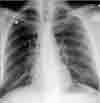

Fever and abdominal pain in man with prior stab wounds: The PA radiograph (A) reveals diffuse miliary lung nodules. There is no evidence of lymphadenopathy or pleural effusion. A chest film obtained 7 days earlier was clear.

The initial manifestation of talc granulomatosis on chest radiographs is a miliary nodular pattern. Although such tiny nodules are individually below the threshold of visibility on chest radiographs, they become visible radiographically when numerous nodules are superimposed on one another (the "stacked coin" effect). CT is much more sensitive than radiography for detecting and characterizing such small nodules.